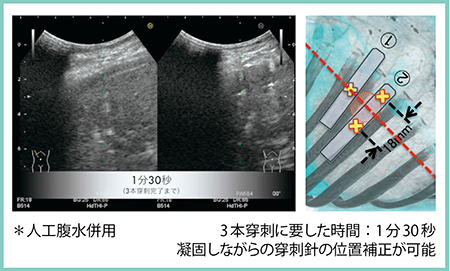

3.平行穿刺法を応用した3本穿刺法:2+1法

2つのプローブを用いて2本の平行穿刺と1本穿刺を組み合わせて行う3本穿刺を「2+1法」と命名した。この時,日立製作所社製の超音波診断装置に搭載されている“Real-time Biplane”機能を用いることで,2つのプローブの画像を並列表示可能にする(図1 左)。実際に穿刺を行ってみたところ,3本穿刺に要した時間は約1分30秒で(図1),焼灼が不十分なところはリアルタイムに針の位置補正も可能であり,治療後のCT画像では十分なマージンを取って焼灼できていることが確認できた。

図1 2+1法における実際の穿刺